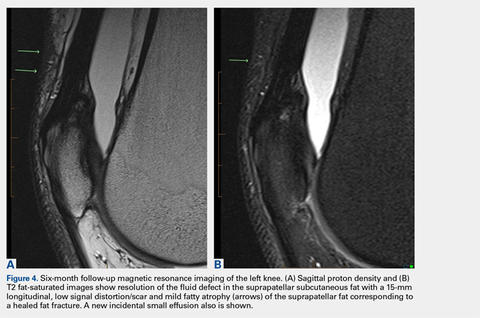

These findings explained the delayed course in resolution of symptoms. Over the next 48 hours, continued conservative management, as outlined above, led to the resolution of symptoms, and the athlete returned to play. At a 2-month follow-up, the athlete described normal function in his knee without any residual symptoms. He returned to play without any symptoms. At 6 months, the athlete underwent MRI of the same knee for an unrelated reason. MRI revealed a healed fat fracture with resolution of the fluid defect in the subcutaneous fat (Figures 4A, 4B).